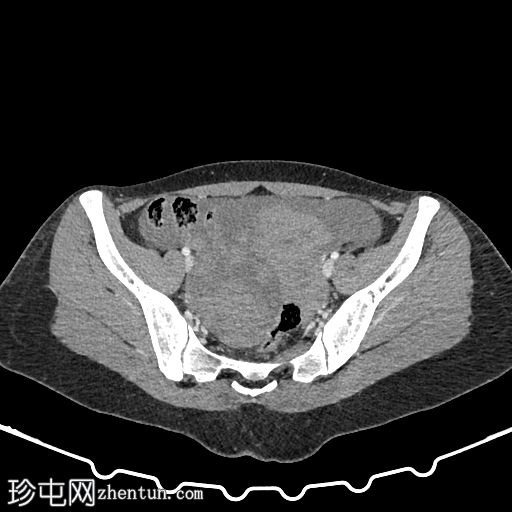

轴位增强扫描(门静脉期)

dr-original.jpg

右侧附件区可见巨大复杂肿块,伴盆腔血肿及腹水。子宫内可见积液。